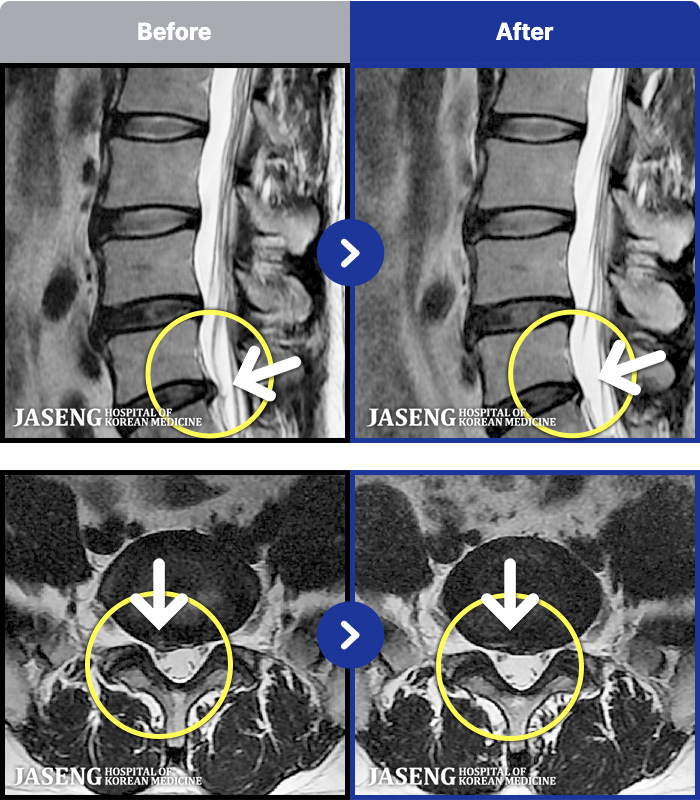

54 MRI ũ ʸ Ȯϼ.